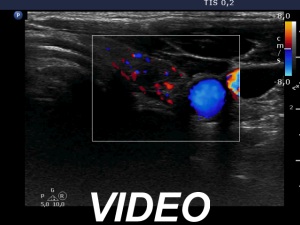

First examination (1st to 3rd rows of images):

Ultrasonography: Both lobes presented hypoechogenic ill-defined areas. The echogenicity index was 80% in the right lobe while 20% in the left thyroid. The vascularization was significantly decreased.

Elastography demonstrated hard areas according to the hypoechogenic field in the left lobe while almost the entire right lobe proved to be hard.Cytological diagnosis: subacute, granulomatous de Quervain's thyroiditis.